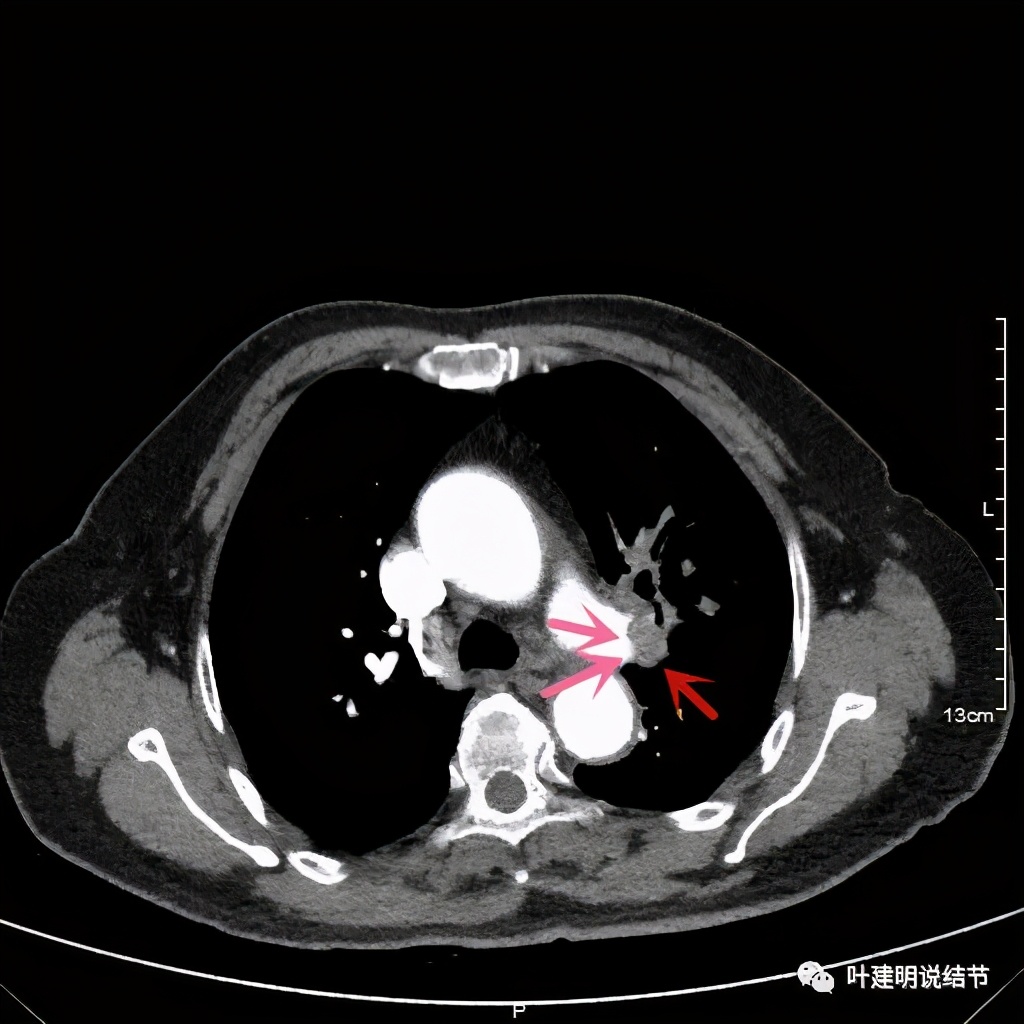

患者手术安排在2021.6.21进行,手术组先胸腔镜进胸探查有无胸壁转移及胸水,评估手术切除的可能性,并在镜下游离下肺韧带、清扫纵隔淋巴结,解剖游离上肺静脉,并将左肺动脉主干游离出来并套阻断带备用,以防解剖过程中出血时控制肺动脉出血。因肺门部原肿瘤部位仍与叶间动脉及上叶支气管、肺动脉分支等愈着紧密:

上图示肺动脉仍与软组织影关系密切,没有间隙可分开

上图示肺动脉与肿瘤的关系仍紧密

上两图示叶间肺动脉的上缘与肿瘤没有界限